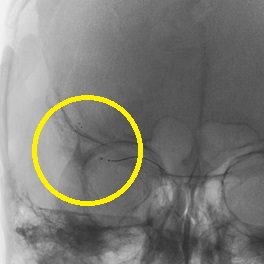

ソリティア(ステント型血栓除去器具)による超急性期血管内治療

突然の意識障害と左半身重度麻痺で発症した右内頚動脈閉塞例。発症から5時間が経過しており、t-PA 治療の適応外であったため緊急で血管内治療を施行。治療開始後速やかに完全再開通を得た。術後左麻痺は残存したが意識障害は回復。

1.緊急MRA検査で右内頸動脈閉塞の診断

2.治療前造影で右内頸動脈の完全閉塞を認める

3.閉塞部遠位までマイクロカテーテルを誘導し造影

4.ソリティアを閉塞部まで誘導し展開

5.手技開始速やかに完全再開通を得た